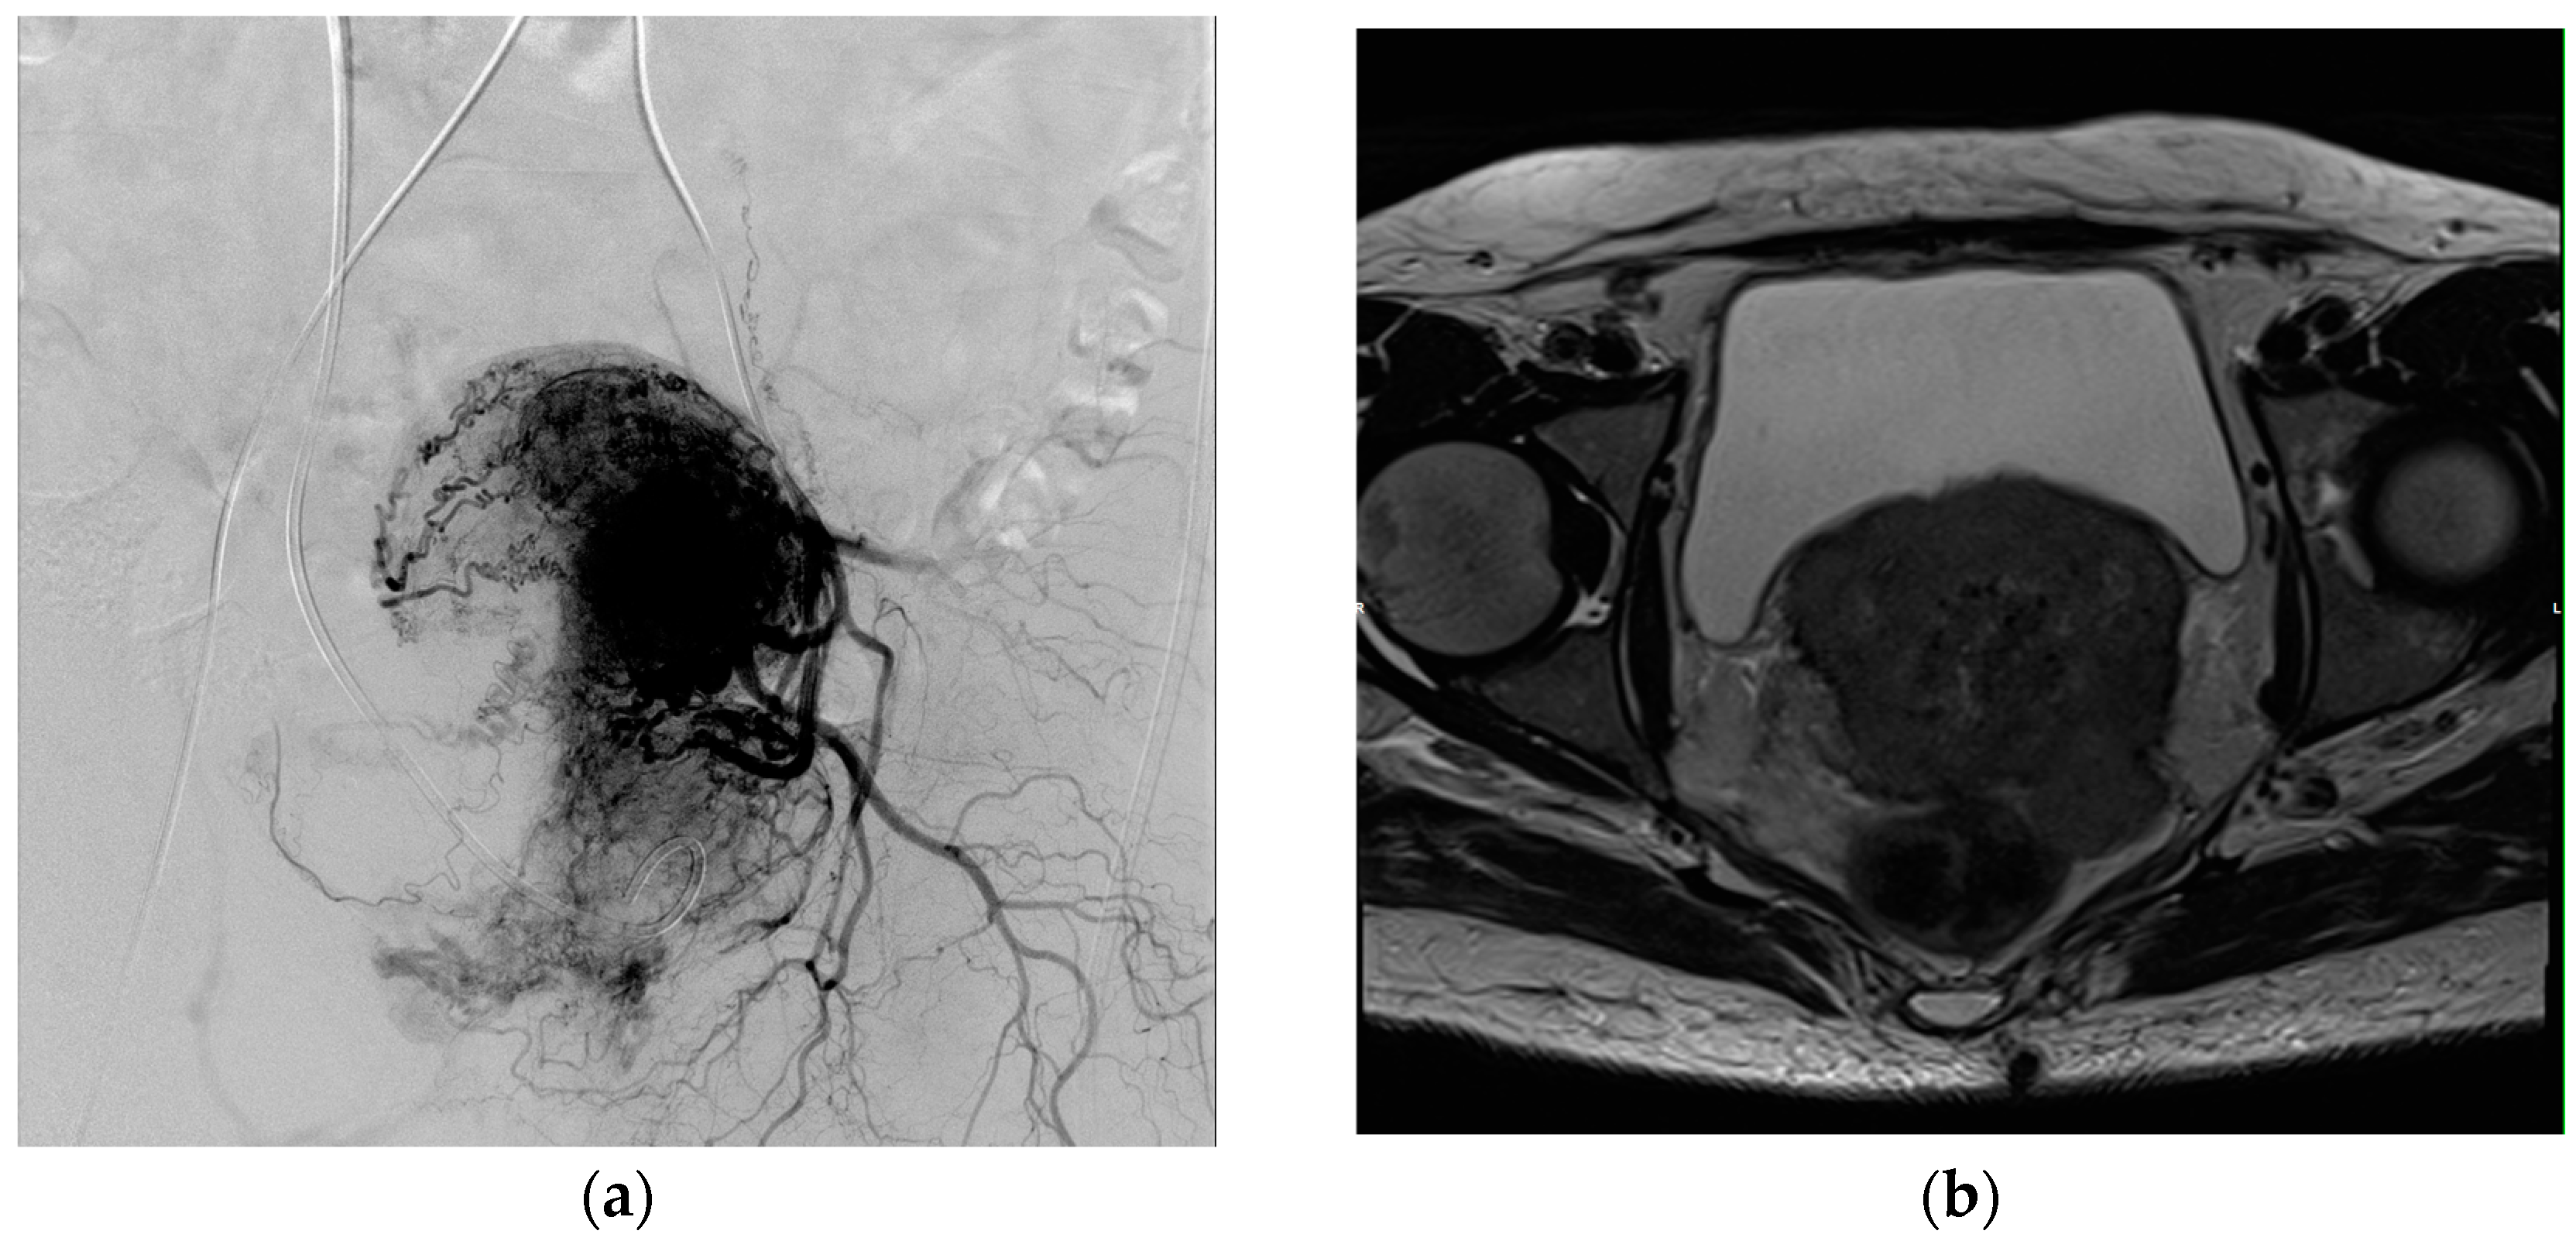

Figure 1. (a) Angiographic image of a transarterial chemoembolization (TACE) procedure in a patient with cervical carcinoma T4N2M1. The catheter was placed in the left internal iliac artery. (b) Transverse T2-weighted MRI image of the pelvis, in which the treated tumor is detectable.